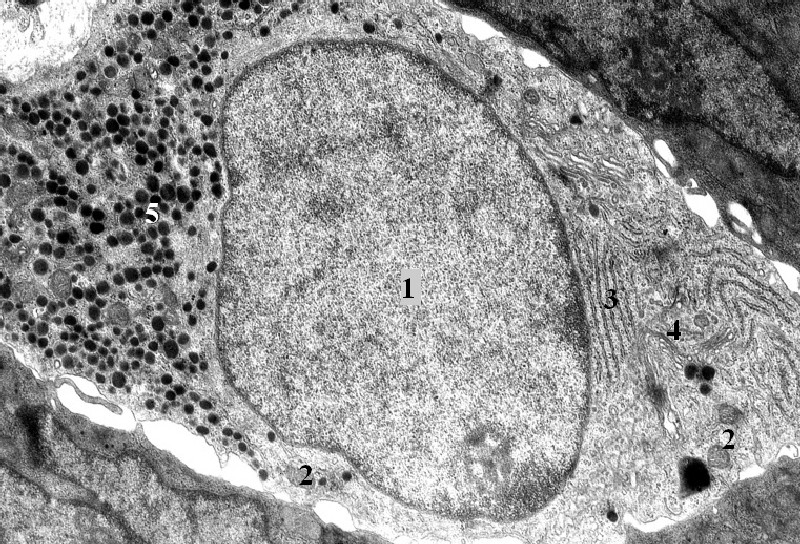

Enteroendokrinní buňka střevního epitelu se zřetelně polarizovanými organelami: jádro (1), mitochondrie (2),

zrnité endoplazmatické retikulum (3), Golgiho komplex (4), vakuoly a sekreční granula (5)